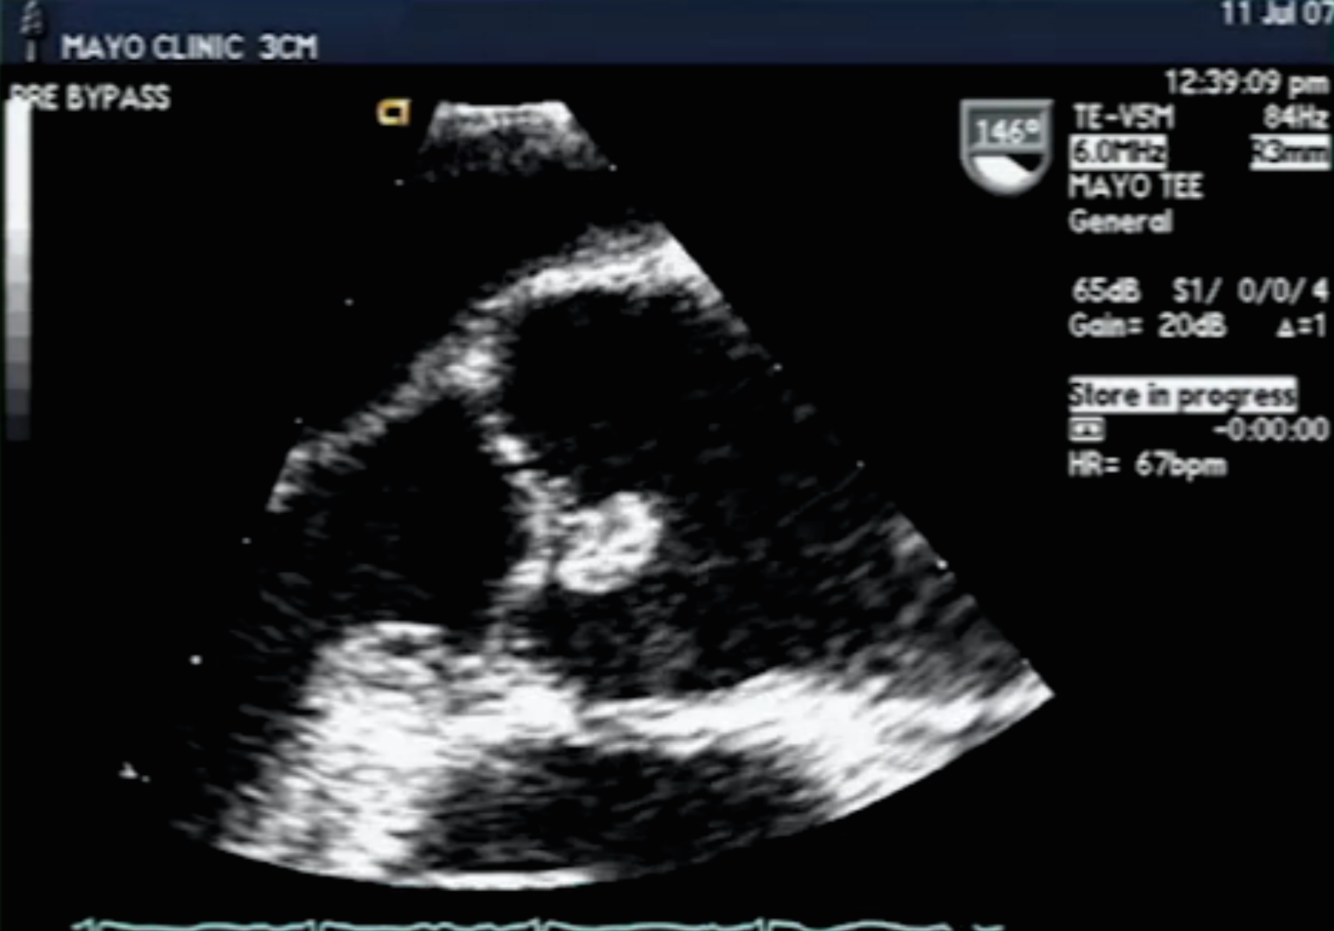

Diagnosis and Rx? (ON BOARD EXAM)

early closure of MV from severe AI (from SBE)- RX = emergent surgery